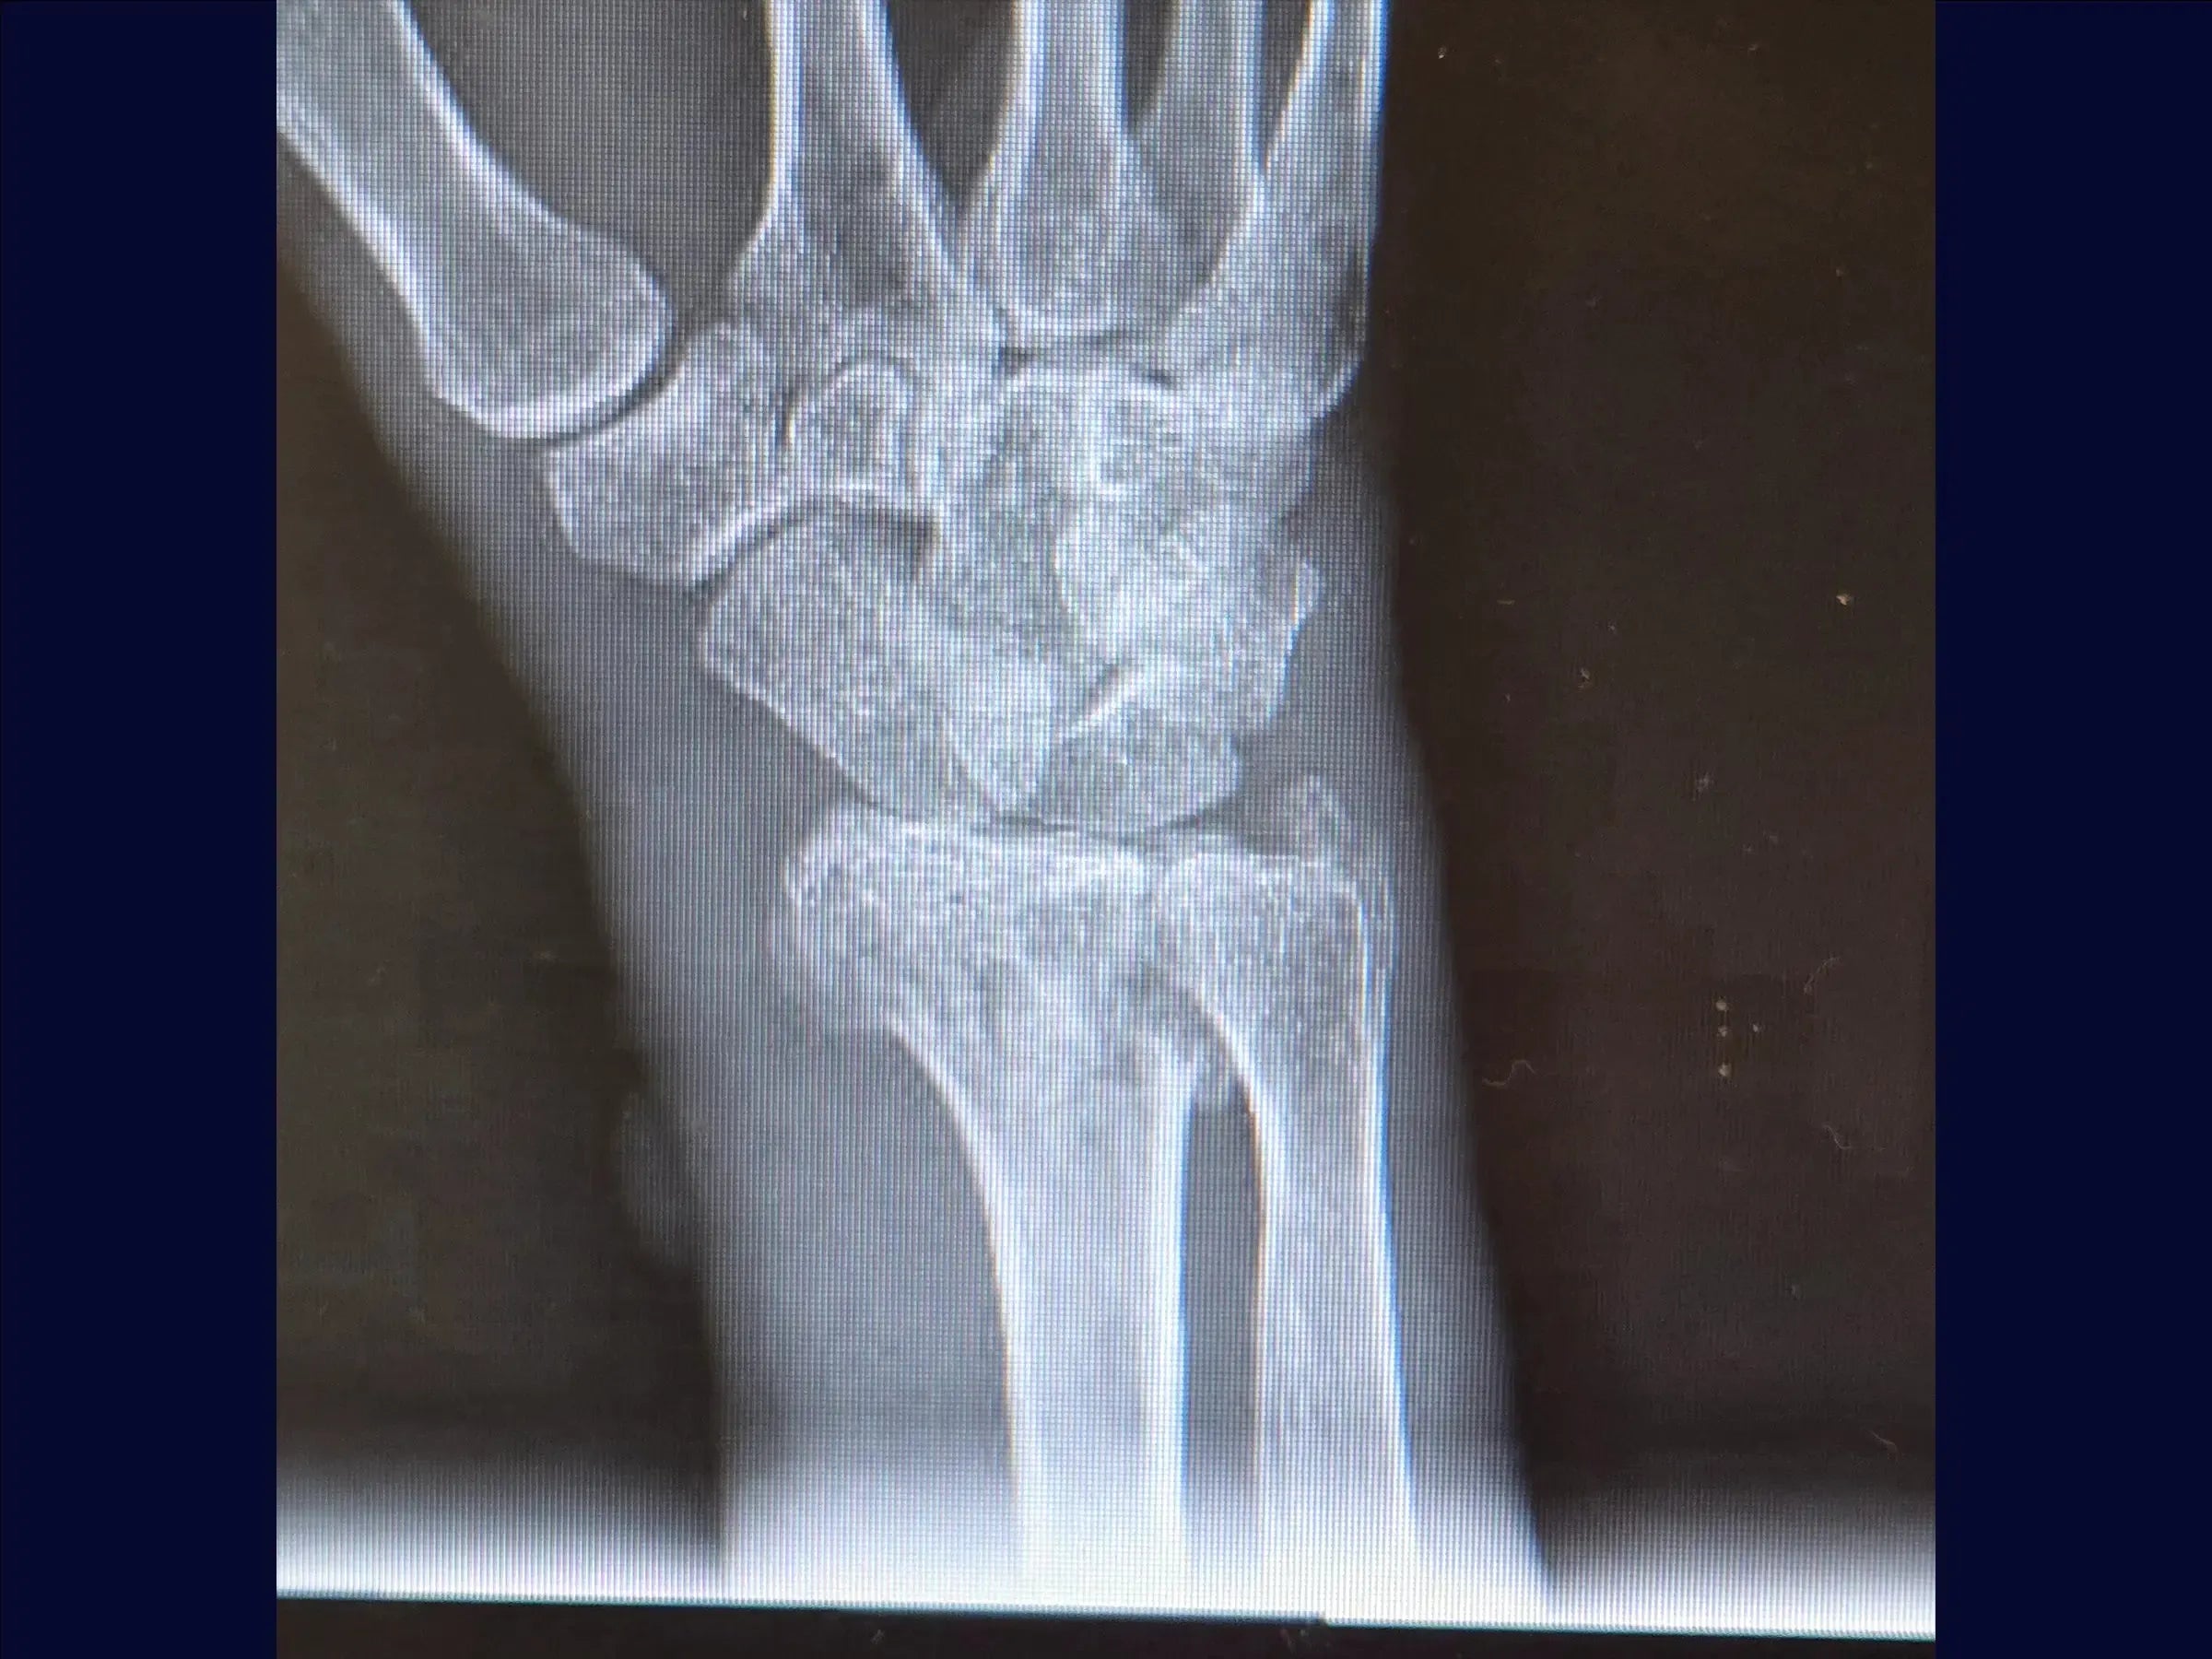

- Evaluación y reducción provisional: La formación abarca el análisis de imágenes de fracturas multifragmentarias del radio distal y la reducción por tracción manual ( ligamentotaxis ). Incluye la fijación percutánea provisional con alambres a la estiloides radial y al tubérculo de Lister para estabilizar los fragmentos.